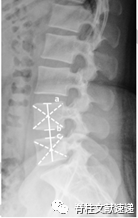

使用CT扫描技术评价PLIF术后椎间融合率和cage下沉率